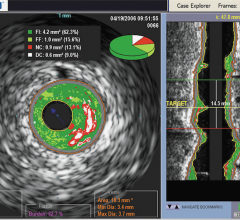

January 21, 2011 – Intravascular ultrasound (IVUS) enabled physicians to more accurately assess the risk of individual blockages than the use of the current standard of angiographic imaging alone, according to a new study.